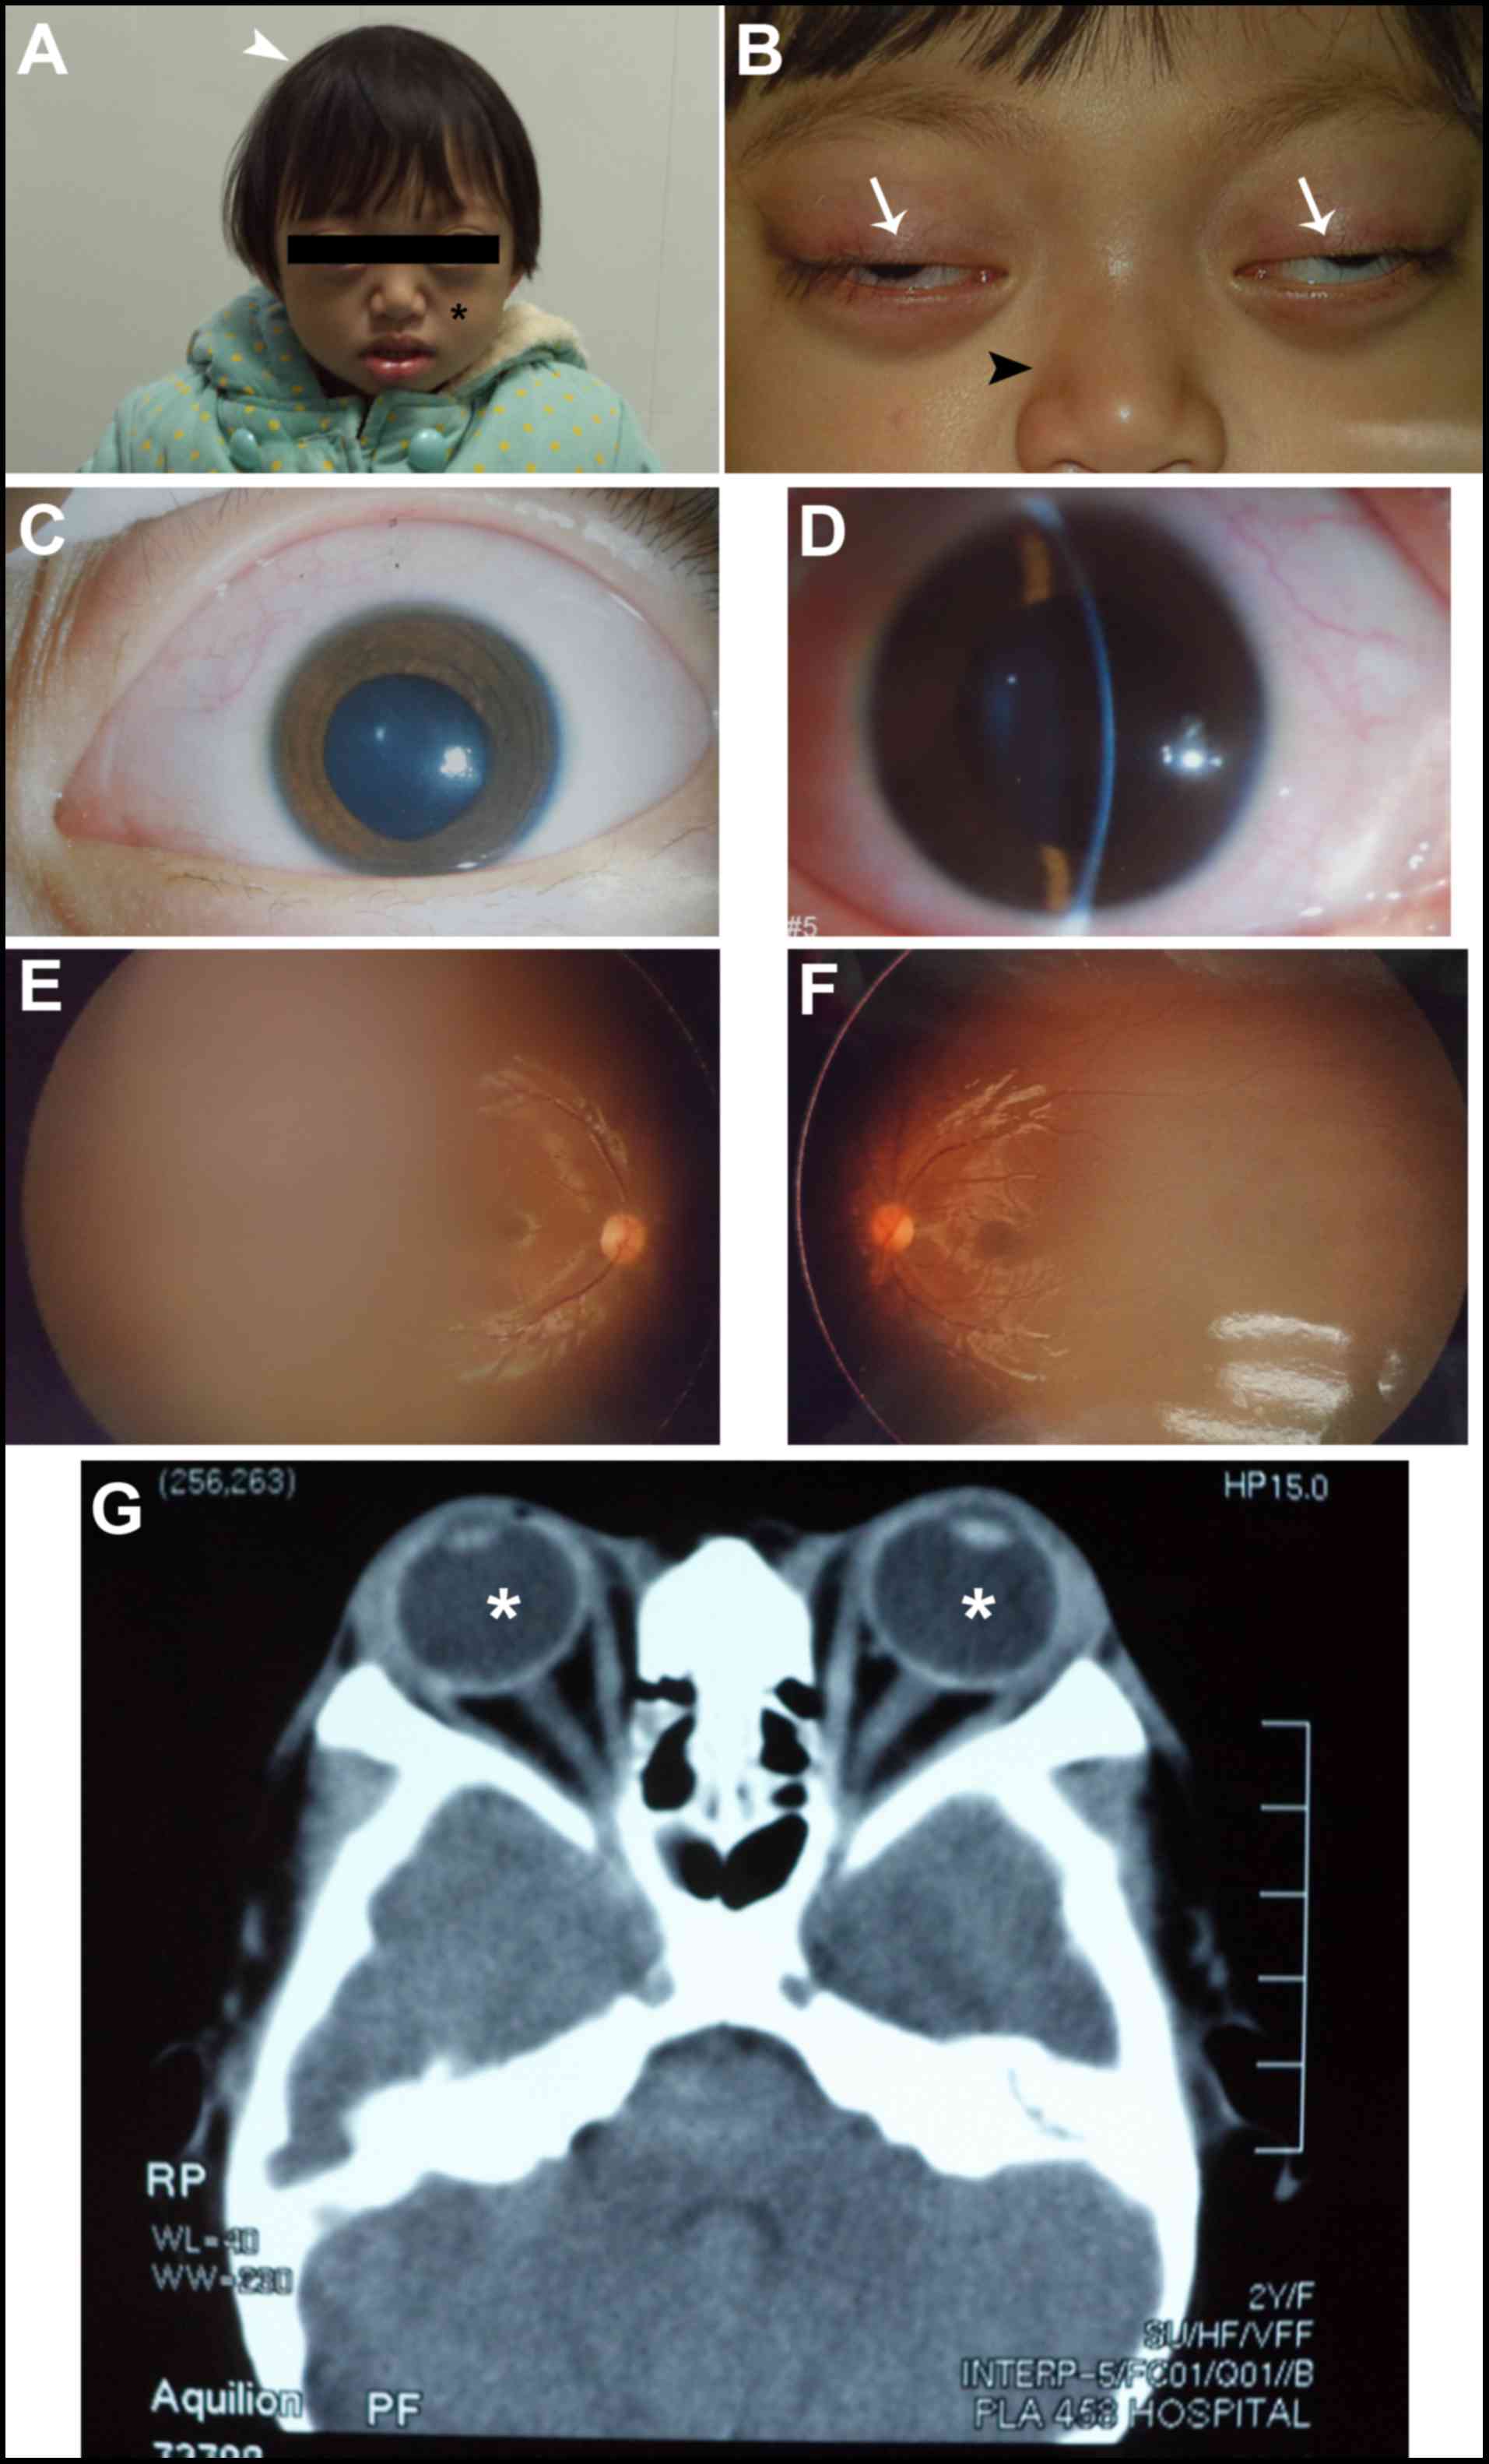

Pontine Tegmental Cap Dysplasia Accompanied By A Duplicated

Fgfr2 Mutations And Associated Clinical Observations In Two